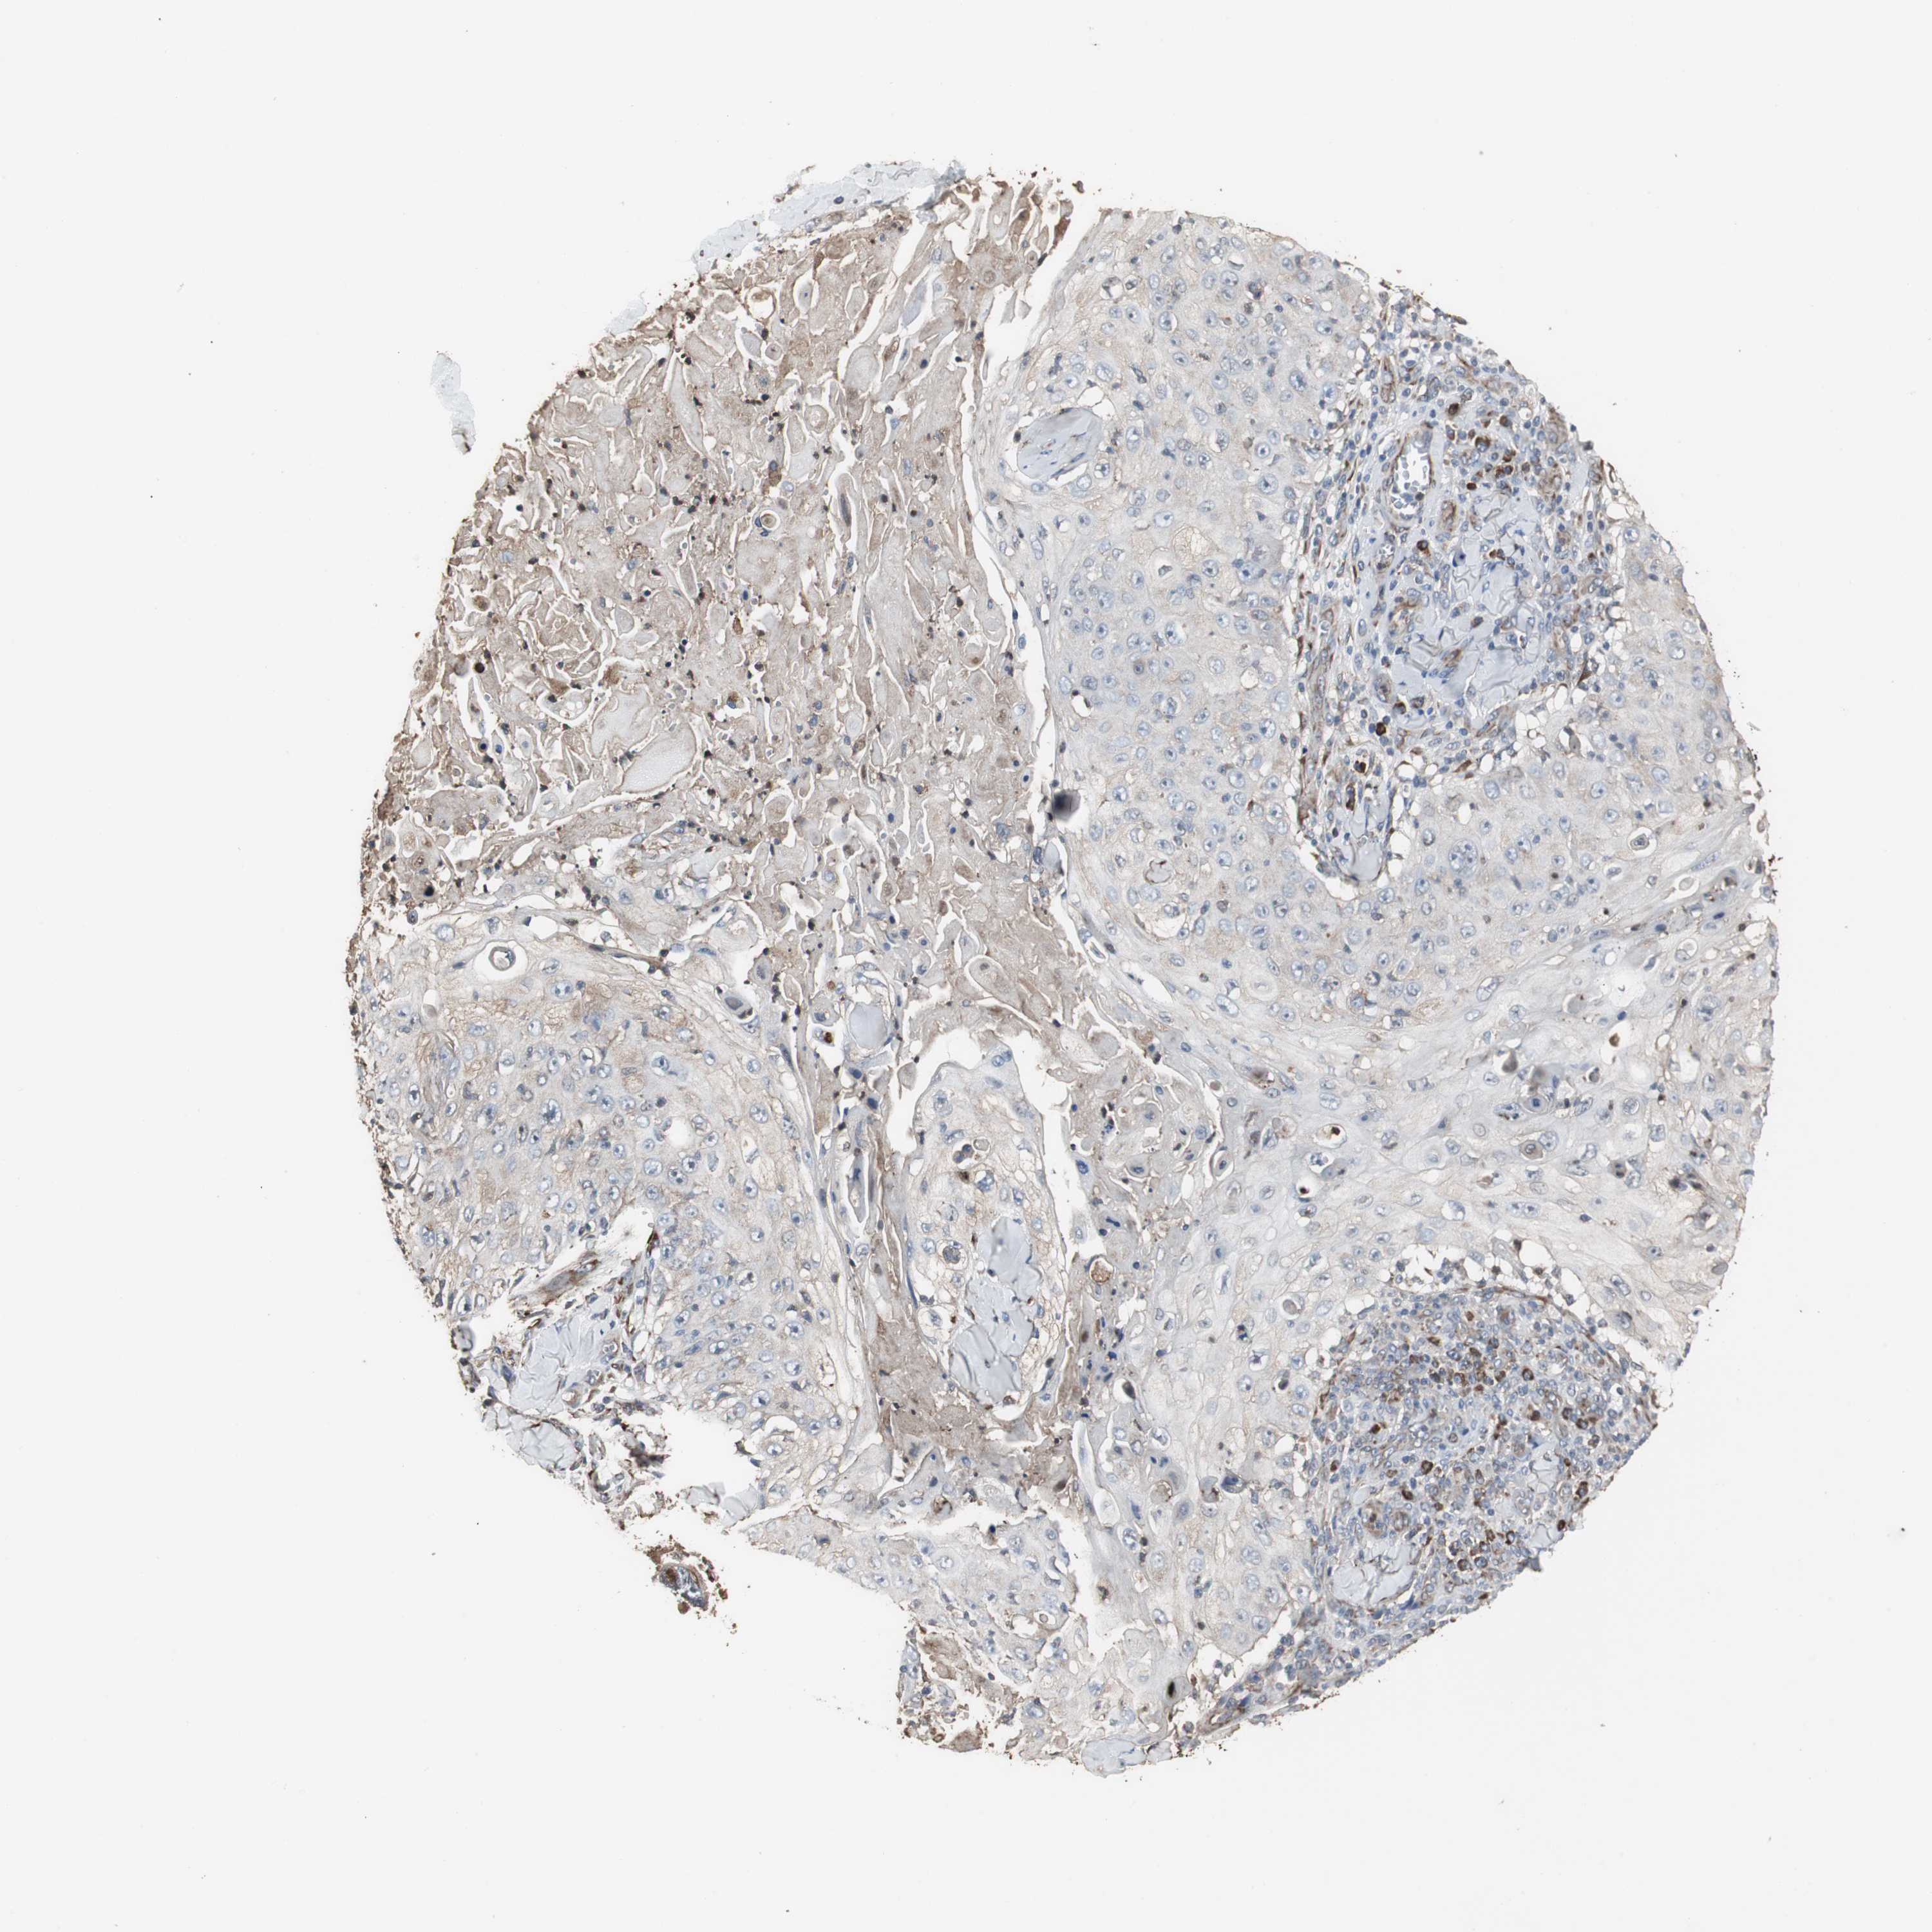

SKIN CANCER - Protein expressioni

A mouse-over function shows sample information and annotation data. Click on an image to view it in a full screen mode. Samples can be filtered based on level of antibody staining by selecting one or several of the following categories: high, medium, low and not detected. The assay and annotation is described here.

Each image is clickable and will lead to virtual microscopy that enables deeper exploration of all samples and also displays staining intensity scores, fraction scores and subcellular localization as well as patient and tissue information for each sample.

Antibody HPA006018

Staining

Medium

Moderate

>75%

Cytoplasmic/membranous

Squamous cell carcinoma, NOS

Basal cell carcinoma